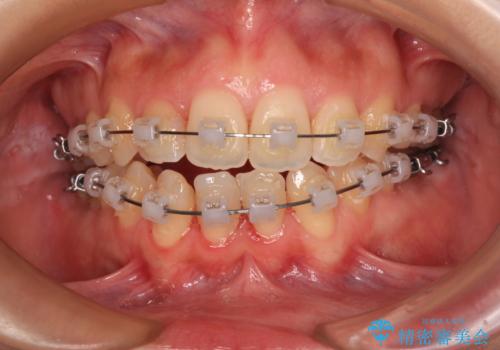

後戻りの再矯正 ワイヤー装置でデコボコと隙間を改善

- クリアブラケット

- 学生時代の抜歯矯正の後戻りが気になり、再矯正を希望して来院された患者様です。

マウスピース矯正は継続する自信がなく、気になるところを短期間で改善したいとのことで、ワイヤー装置にて矯正治療を行うこととしました。

詰め物で隠していた下顎前歯の隙間は、歯軸を改善することで詰め物を除去しても隙間が目立たなくなりました。

まだ改善したいところはありましたが、患者様自身は大変満足されたとのことで、治療を終えることとなりました。